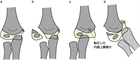

1. 初診日の転位量が2.0mm未満であった17例は、前腕回内、肘屈曲96~120°で外固定し、全例骨癒合。可動域も良好。

転位量2mm未満の小児上腕骨外側顆骨折は、不適切な外固定が行われて転位することも多いが、前腕回内肘関節鋭角屈曲位での適切な外固定を行えば問題なく治癒することがほとんどである。